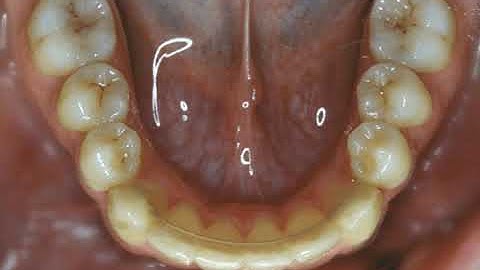

Evaluation of Tooth Movement Path Using CBCT